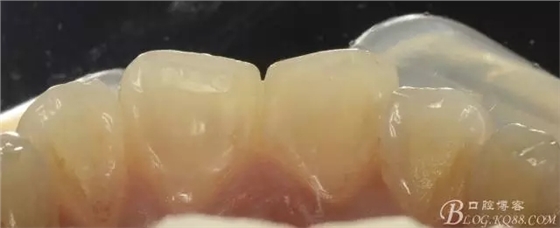

舌側(cè)觀

去腐后舌側(cè)照片:

沒有牙本質(zhì)支撐的釉質(zhì)是多么的晶瑩剔透,透得你舍不得傷害它!

不同參數(shù)下拍攝的舌側(cè)觀: